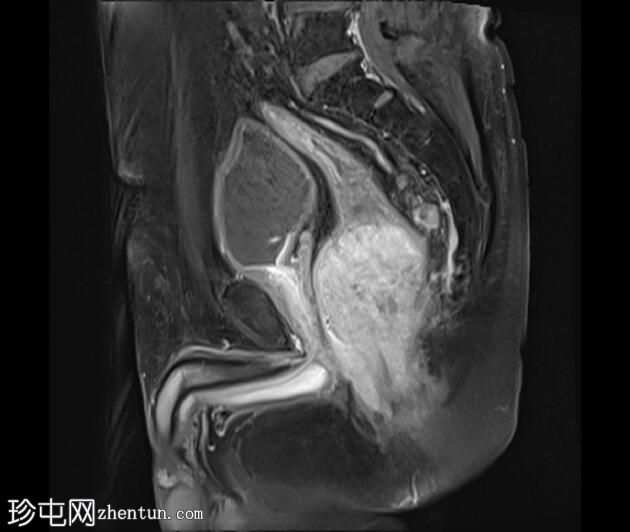

矢状位

7.jpeg

T1加权像

可见一不规则分叶状肿块,累及直肠中段和远端,头尾方向长约7 cm,下缘距肛缘约2.5 cm。在T1加权像和T2加权像上,该病灶相对于骨骼肌均呈高信号。 PDFS(脂肪抑制)图像显示持续高信号强度,提示存在黑色素和/或出血成分。

增强扫描显示病灶内呈不均匀强化。直肠下段7点钟位置的系膜筋膜受累。后方系膜可见少量淋巴结。未见邻近器官侵犯。